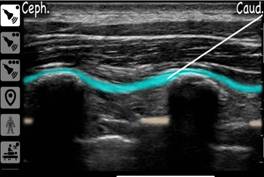

- Thuốc tê được tiêm dưới hướng dẫn của siêu âm, đảm bảo độ chính xác cao. Thuốc lan tỏa dọc theo mặt phẳng cơ dựng sống, phong bế các nhánh thần kinh lưng và liên sườn, giúp giảm đau ở cả vùng ngực trước và sau.

Một số hình ảnh về phương pháp ESP Giảm đau sau mổ Patey vú được triển khai tại bệnh viện Ung bướu Thanh hóa.

Hình 1: Vị trí tiêm phong bế ESP

Hình 2: Bác sĩ thực hiện ESP dưới hướng dẫn siêu âm